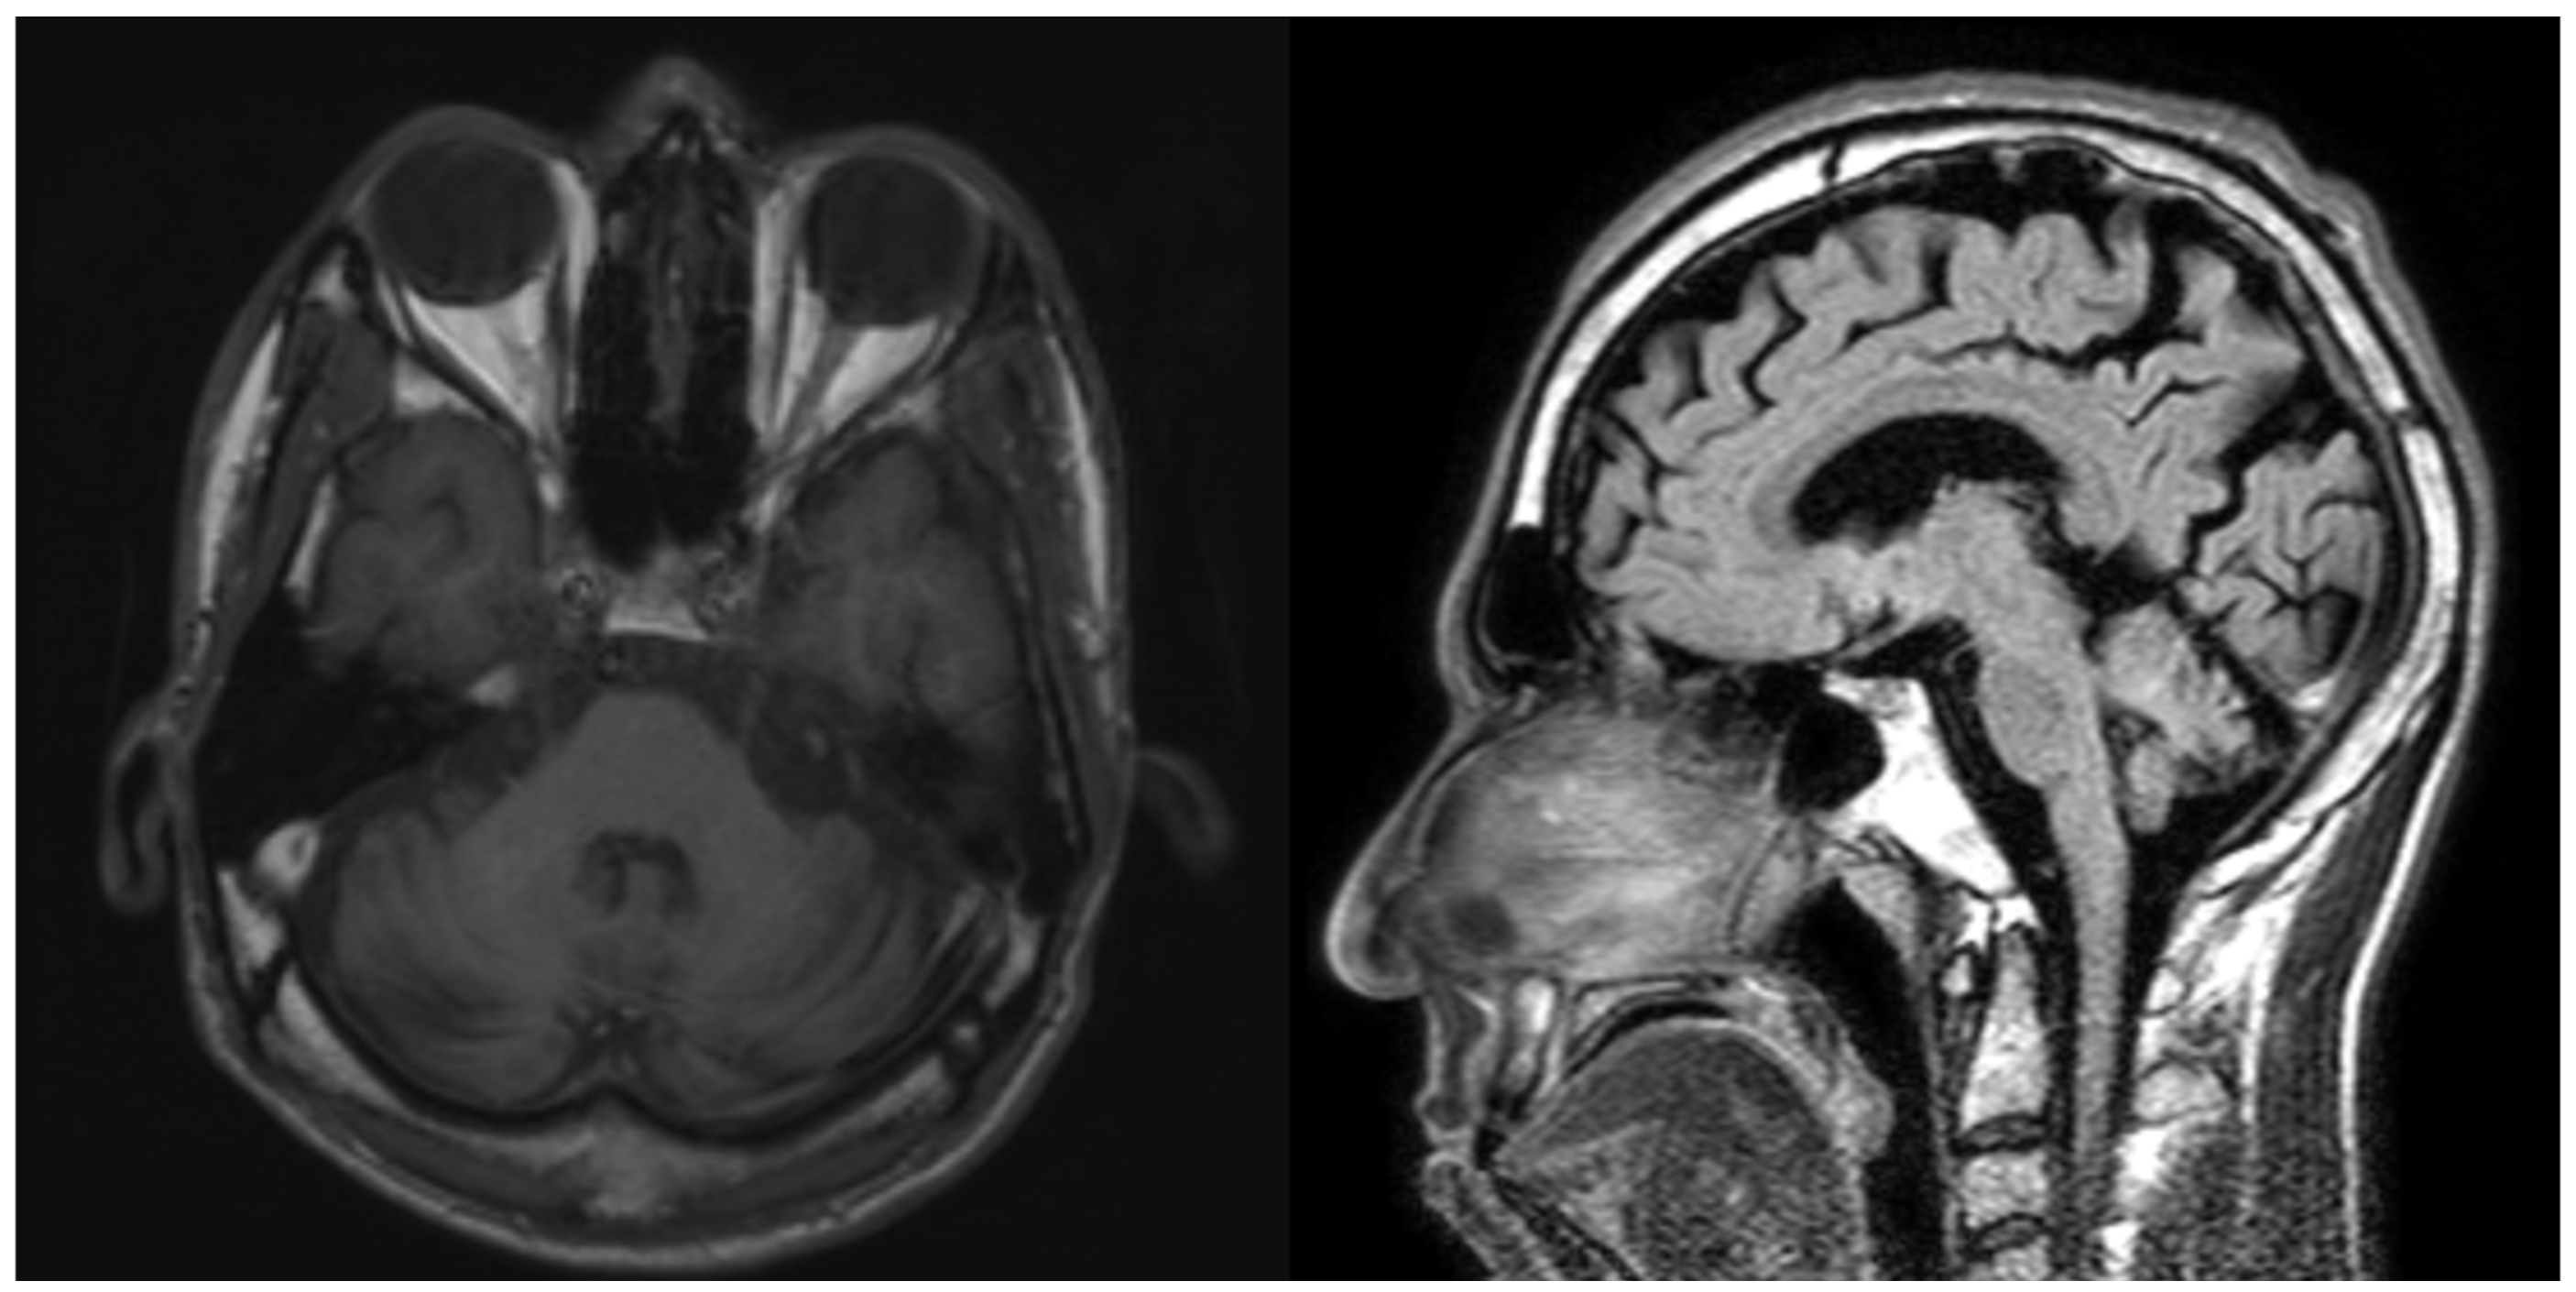

Laboratory studies, including serum heavy metal levels, TSH, and peripheral blood smear, were unremarkable. Huntington’s disease was excluded with normal Huntingtin levels. Brain MRI showed cerebellar atrophy of both hemispheres and vermis, as well as corticosubcortical cerebral atrophy with ventricular dilation due to brain volume loss [figure2].

Figure2